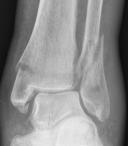

Ankle fractures

Ankle fractures |